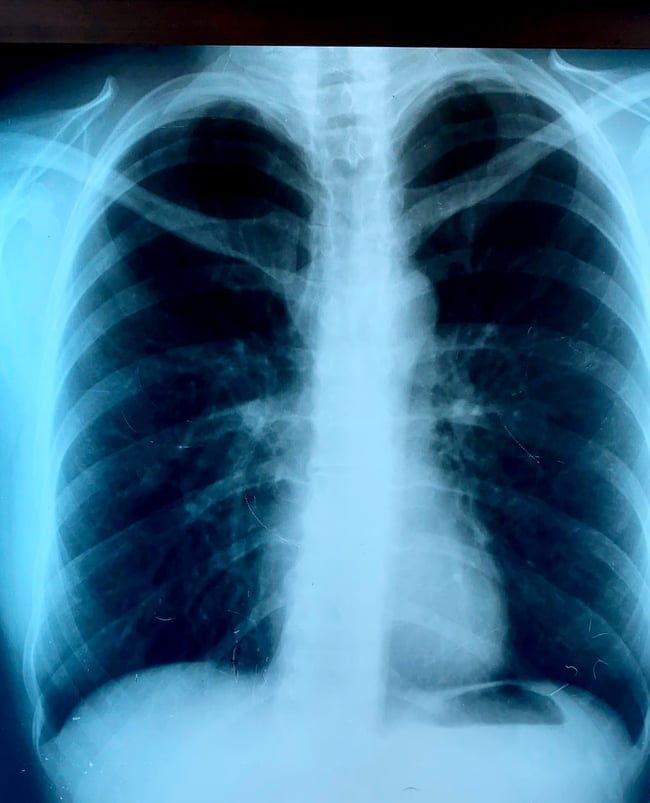

7.Dijagnoza se postavlja na osnovu anamneze gde su presudni podaci o pušenju ili velikoj izloženosti aerozagađenju na radnom mestu i životnoj sredini. Za utvrđivanje sigurne dijagnoze i stepena HOBP koristi se spirometrijski test,analize krvi, rendgenski snimci i CT-skene pluća⬇️

ugrožena', ali je pojasnila i kako dolazi do izuzetno teških slučajeva u kojima se 'čak i za nekoliko sati razviju ekstremno teške pneumonije'.Zabrinjavajuće su slike koje vidimo u medijima – rtg snimke oboljelih osoba koje ljekari opisuju sa ”pacijent gotovo i nema pluća”⬇️.